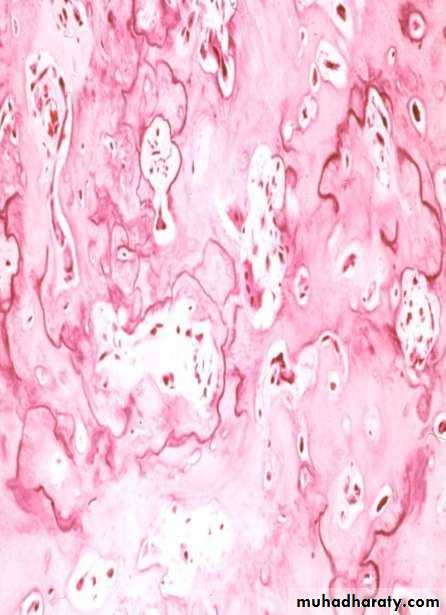

• Histopathology:

• Conglomerate of cementum which often contain reversal line and cells are enclosed in lacunae.• Peripheral zone has unmine ralized tissue while the center more mineralized .

• Intervening soft tissue is loose very cellular and vascularized, contain multinucleated cementoclast and cementoblast.

• Reversal lines